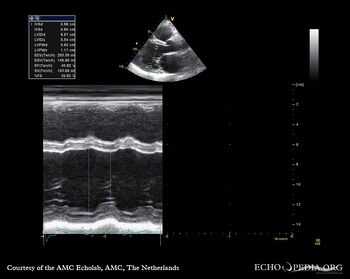

Dilated cardiomyopathy with severe mitral valve regurgitation

Courtesy of: J. Vleugels, AMC, The Netherlands